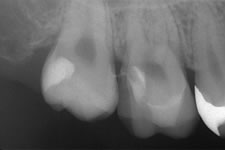

症例紹介

術 前 術 中 術 後

オーキッド|虫歯治療② オーキッド|虫歯治療⑤ オーキッド|虫歯治療③ オーキッド|虫歯治療④ オーキッド|虫歯治療⑥